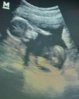

En tiedä miksi sitä vieläkin niin kovasti jännittää, kun ollaan näinkin turvallisilla viikoilla. :)

Ei siis ollut mitään hajua että miten selvästi ne näkyy mutta kyllähän nuo nyt erottaa. Ei sulla ois laittaa vielä kokokuvaa niin hahmottaa vähän että miten se vaava siinä on?